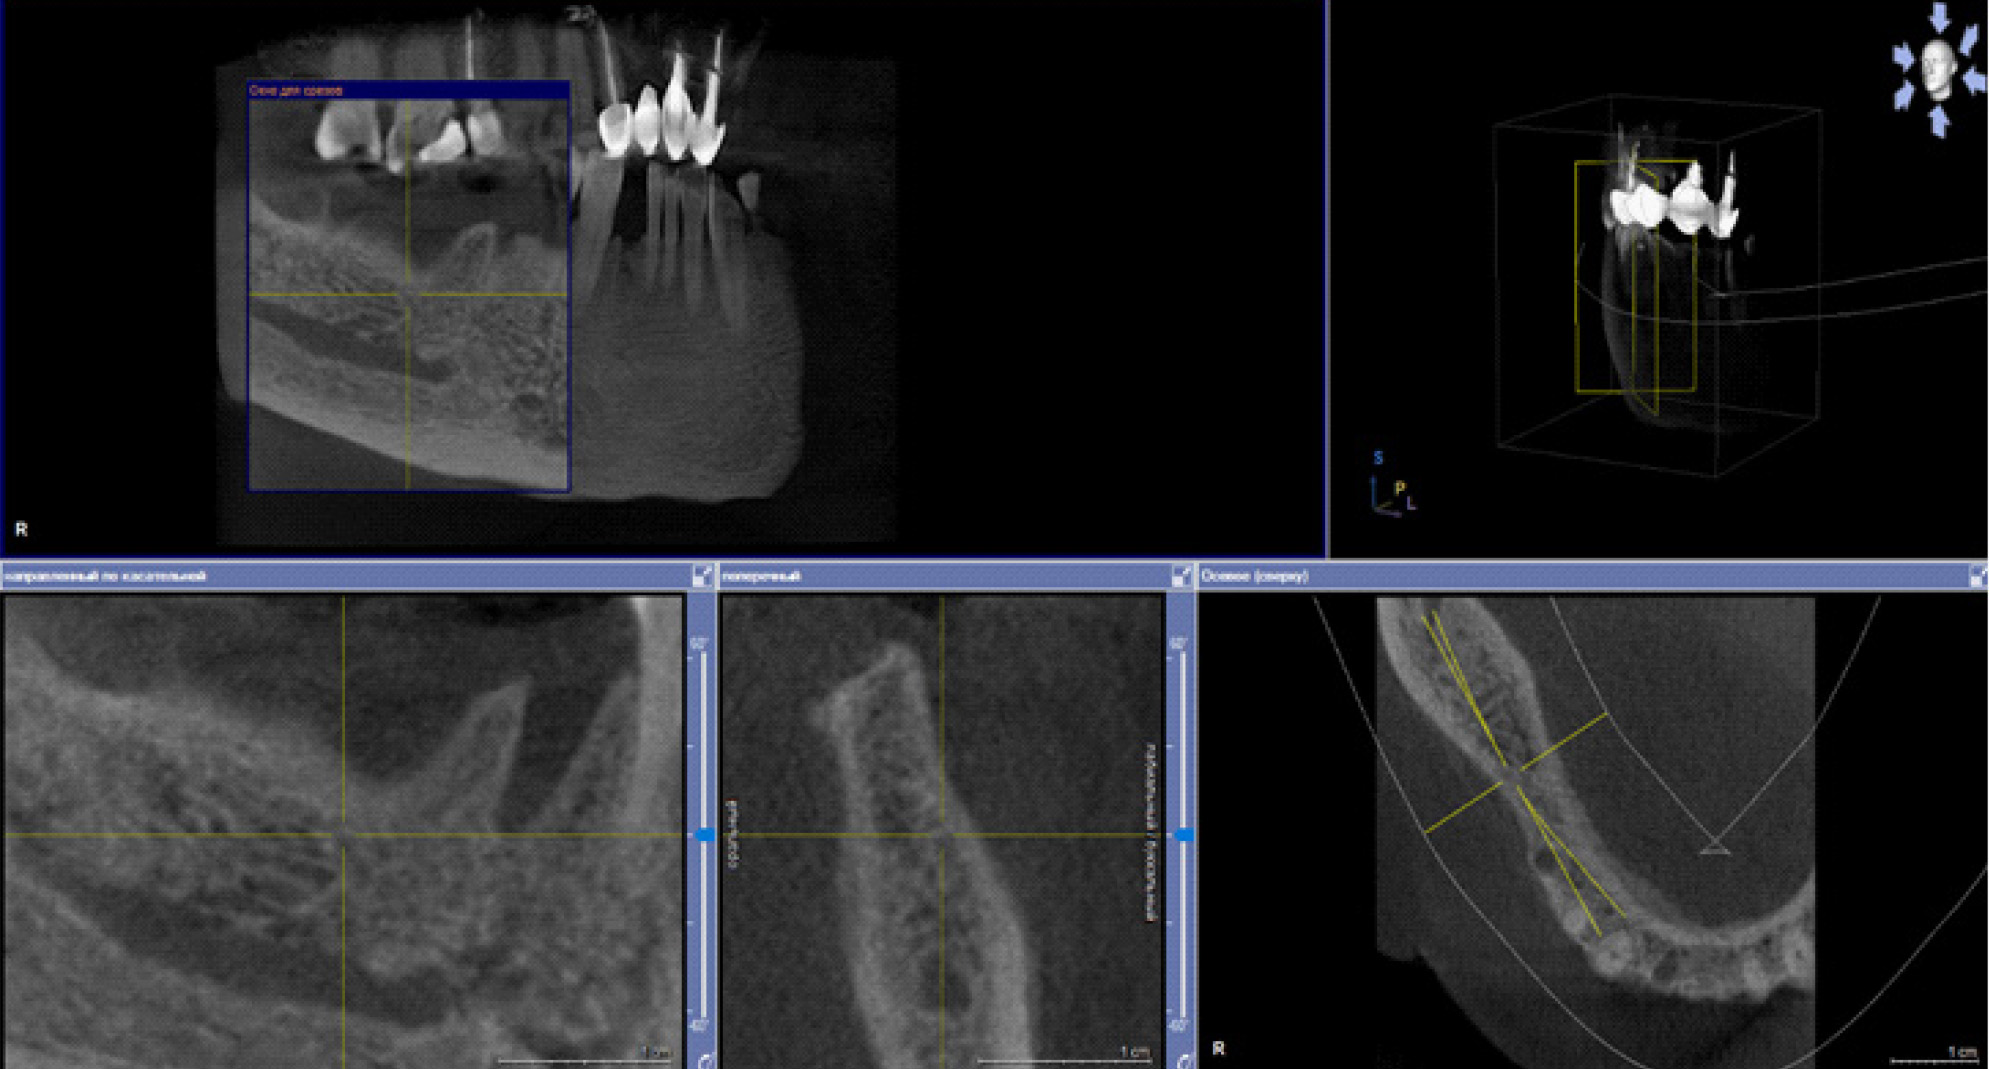

В настоящее время выделяют два основных подхода к лечению БФОНЧ, к ним относятся консервативный и хирургический подход. Выбор тактики лечения пациента зависит от стадии заболевания. Консервативное лечение предусматривает назначение пациентам курсовой антибактериальной, симптоматической терапии препаратов для улучшения микроциркуляции, ежедневной обработки очагов поражения костной ткани растворами антисептиков, частичная некроэктомия, удаление подвижных секвестров, а также тщательное соблюдение гигиены полости рта (рис. 4).

Рис. 4. Компьютерно-томографическое исследование на этапе лечения остеонекроза нижней челюсти справа у пациентки Б. в 2023 г.